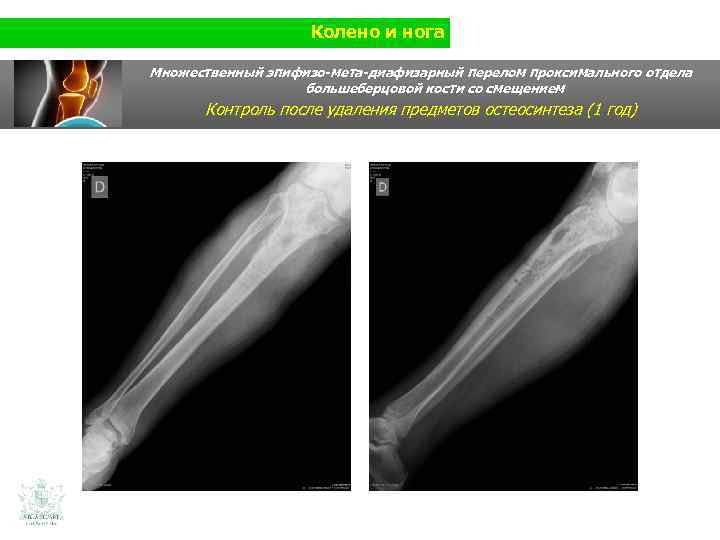

Колено и нога Множественный эпифизо-мета-диафизарный перелом проксимального отдела большеберцовой кости со смещением Контроль после удаления предметов остеосинтеза (1 год)